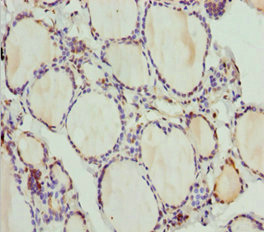

Immunohistochemistry of paraffin-embedded human thyroid tissue using CSB-PA864016DSR1HU at dilution of 1:100